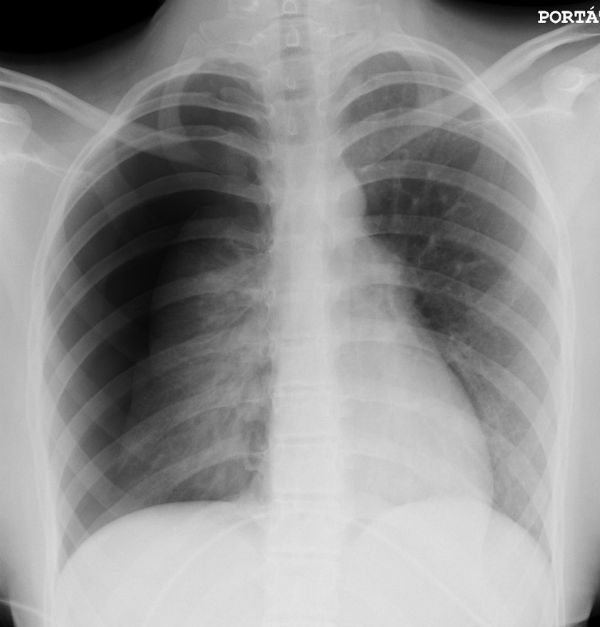

Niño de 15 años con dolor torácico derecho súbito.

Se manifiesta con diferente imagen según si la radiografía se realiza en bipedestación o decúbito. En la radiografía en bipedestación observaremos un área hiperlucente periférica sin marcas vasculares, delimitada por una línea correspondiente a la pleura visceral. Cuando el neumotórax es grande y el pulmón se colapsa en mayor grado, observaremos mayor desplazamiento mediastínico, aplanamiento del diafragma y ensanchamientos de los espacios intercostales.